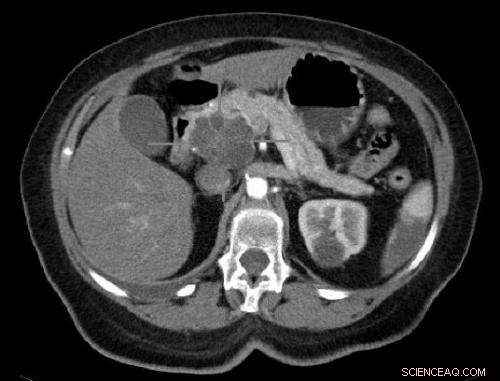

Axial CT image with i.v. contrast. Macrocystic adenocarcinoma of the pancreatic head. Credit: public domain

Pancreatic cancer, a devastating disease with a five-year survival rate of 5 percent, is difficult to detect early and symptoms do not usually appear until the disease is advanced. As a result, many people are not diagnosed until their tumors are beyond the effective limits of surgery, leaving chemotherapy as the only viable treatment option. The chemotherapy drug most often used for pancreas cancer is gemcitabine, but its impact is often limited.